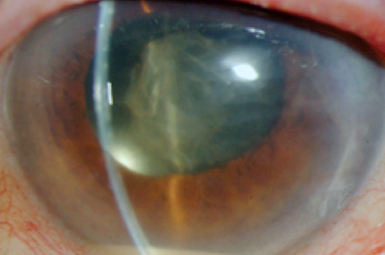

Vitreous Hemorrhage

Vitreous Hemorrhage can be associated with many underlying conditions. It frequently clears on its own, but sometimes necessitates surgical removal.

Vitreo-macular Traction

Incomplete vitreous separation sometimes tugs on the macula. If non-resolving, surgery (or intravitreal medicine) usually rectifies this condition.